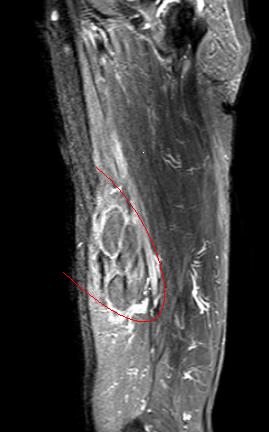

磁共振提示右腿部包块

磁共振示右腿肌内/肌间占位灶